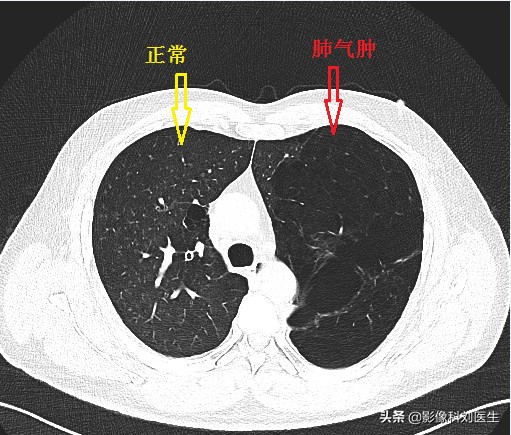

首先给大家看几张CT图像:

通过上面的图像,相信大家有了一个大概的印象。肺气肿主要征象即为正常肺组织内出现无囊壁的低密度区。